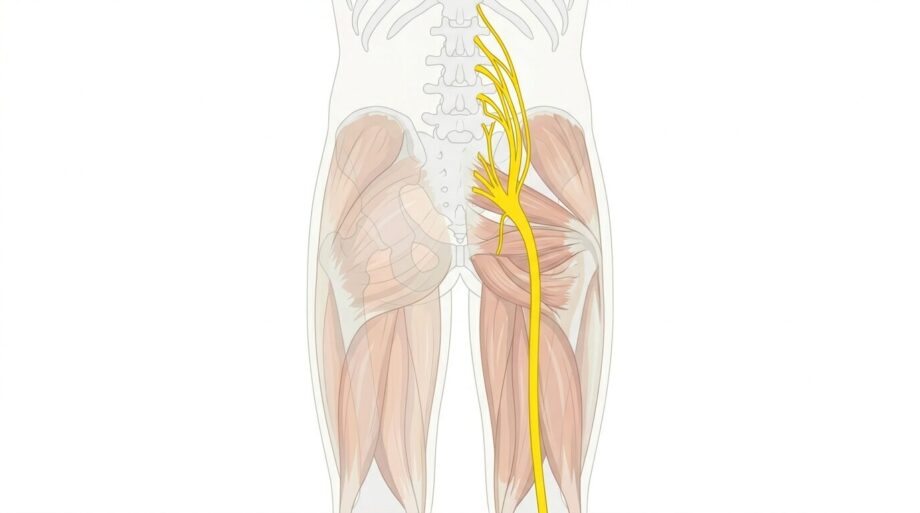

坐骨神経とは、そもそもどのあたりの神経のことを言うかご存知ですか?

ほとんどの方は、お尻から足にかけての神経だと思っているのではないでしょうか?

実はこれは半分正解、半分不正解です。

正解は坐骨神経のスタート(仙骨神経叢)は脊柱から始まり、腰や骨盤の間を抜けて走行していきます。

詳しい場所で言うと、脊髄から分岐した神経が腰椎の下部(椎間孔)と仙骨(骨盤)の裏側の仙骨孔と呼ばれる穴から出てくるのが始まりです(L4ーS3)

腰椎や仙骨(骨盤)裏側から出てきたにもかかわらず、1度骨盤の内側に入っていきます。

このまま骨盤の前側のほうに抜けていきそうですが、そこからまた行く先を変え、仙骨と腸骨の間にある大坐骨孔と言う穴を抜けて身体の後ろ側に戻ってきます。

そこから先は、みなさんの想像されるであろう場所を通っていきます。

お尻の梨状筋と言う筋肉の間を抜けて、お尻の下、太ももの裏へと流れていきます。

その後、膝の裏あたりまでまっすぐと進み、その先は「脛骨神経(けいこつ)と総腓骨神経(ひこつ)」と分岐していきます。

時々ふくらはぎがしびれると言う方で、坐骨神経痛だとおっしゃる方がいますが正確にはこれは坐骨神経のつながりである、脛骨神経痛と言う症状になります。(まぁ坐骨神経痛の方が一般的には伝わりやすいとは思いますが…^^;)